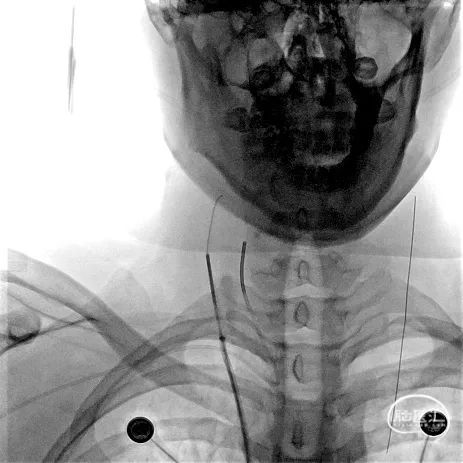

a) 经桡动脉造影明确病变情况:术中行右侧桡动脉及右侧股静脉双穿刺,动脉入路完成评估,静脉入路作为治疗通道,经桡动脉造影评估静脉期上矢状窦及横窦情况,明确上矢状窦、右侧横窦血栓形成。同时经颈静脉置入Neuron Max导引导管,逆行而上接近颅底破裂孔区。

2A

2B

图注2:

2A 桡动脉入路,5F Simmons造影管超选右侧颈内动脉行造影评估,股静脉置入8F穿刺鞘,Neuron Max(0.088inch)在125cm MPA配合泥鳅导丝引导下进入右侧颈静脉。

2B 脑动脉造影静脉期可见上矢状窦显影不清,明确静脉窦血栓诊断。